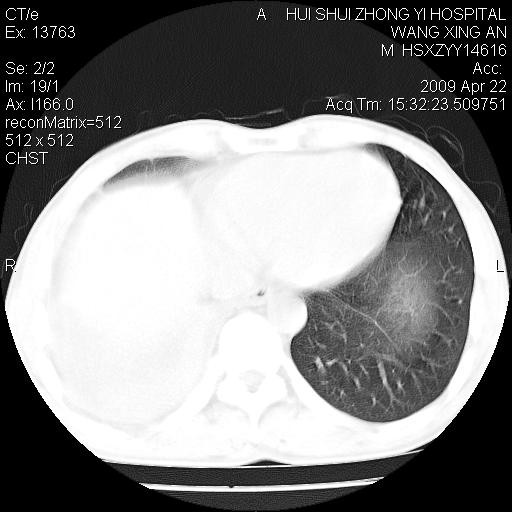

标题: CT19534:患者男、46岁咳嗽、胸痛半月。 [打印本页]

标题: CT19534:患者男、46岁咳嗽、胸痛半月。

考虑---右肺中心型肺癌继发下叶不张,少量胸水。

支持右侧中央型肺ca并右下肺不张、右侧胸腔少量积液。

1、右下肺中央型肺癌并右肺转移,右肺下叶不张。(右肺有结节影)。

2、右中上肺陈旧性肺结核(因为大多为纤维灶)。

3、右侧胸腔积液。

1、右下肺中央型肺癌并右肺转移,右肺下叶不张。(肿块围绕右肺下叶支气管生长,致管腔闭塞右肺下叶不张;右肺有结节影)。

2、右侧胸腔积液。

3、右中上肺陈旧性肺结核(右肺见纤维化病灶及点状钙化)。